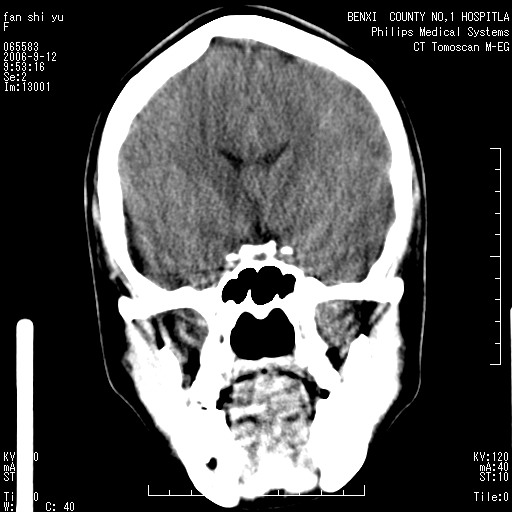

标题: CT4607:看看这个头颅冠状位。

女,22岁,自觉头顶部质硬包块.

巨大蛛网膜粒压迹。

巨大蛛网膜粒压迹